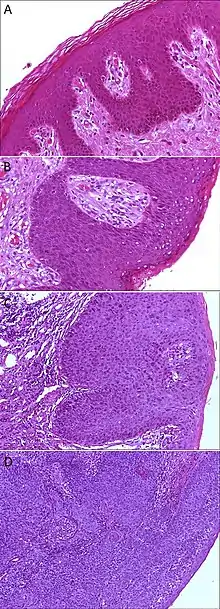

Histopathology of anal epithelium:[1]

A. Normal histology, negative for anal intraepithelial neoplasia lesion (AIN)

B. Low-grade dysplasia, here called low-grade squamous intraepithelial lesion (LSIL)

C. High-grade dysplasia, here called high grade squamous intraepithelial lesion (HSIL)

D. Squamous cell carcinoma, infiltrating the stroma (middle and left in image), and HSIL (right in image)